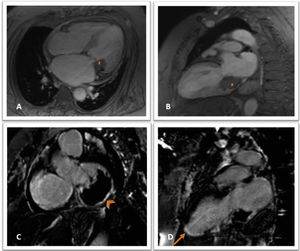

Cine gradient echo magnetic resonance imaging sequences in 4-chamber (A) and 2-chamber view (B), showing a hypointense mass (star) in the inferior and lateral region of the mitral annulus, extending to the inferior basal segment; delayed postcontrast images showing late enhancement at the periphery of the lesion (C, arrowhead) and transmural late enhancement in the inferior mid-apical and apex segments (D, arrow).

This case illustrates the complementary role of multimodality imaging in a challenging diagnosis of caseous necrosis of the mitral annulus, in a patient with a cardioembolic infarction. While TTE identified the presence of the mass and its functional significance, CT confirmed its calcified nature and MRI was essential for excluding other potential etiologies as well as to confirm the infarction scar.